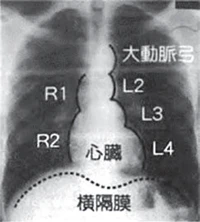

心陰影所見

心臓・大血管の形や大きさなどに異常があるかどうかを調べます。

X線写真上の心臓は、ほぼ中央から左よりに白い卵形の影としてみえます。これが心陰影で、何らかの変化がみられた場合に所見名がつきます。

判定がBであれば特に心配ありませんが、判定がE1の場合は心臓超音波検査等の精密検査が必要です。